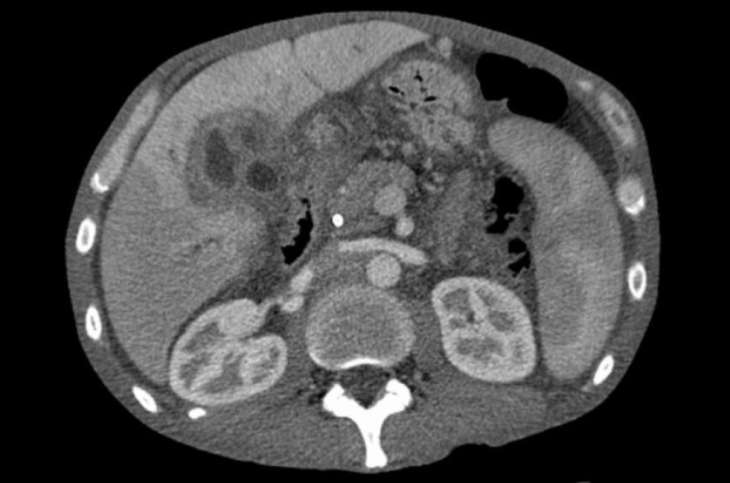

Вчені говорять, що метастази або сама пухлина дратують відповідні нерви, які посилають у мозок помилковий сигнал про біль у лопатці. Насправді болючі відчуття виходять з печінки. При цьому найчастіше біль у правому плечі, але у виняткових випадках може поширюватися по всій спині. Наголошується, що симптоми раку печінки часто не виявляються на ранніх стадіях захворювання.